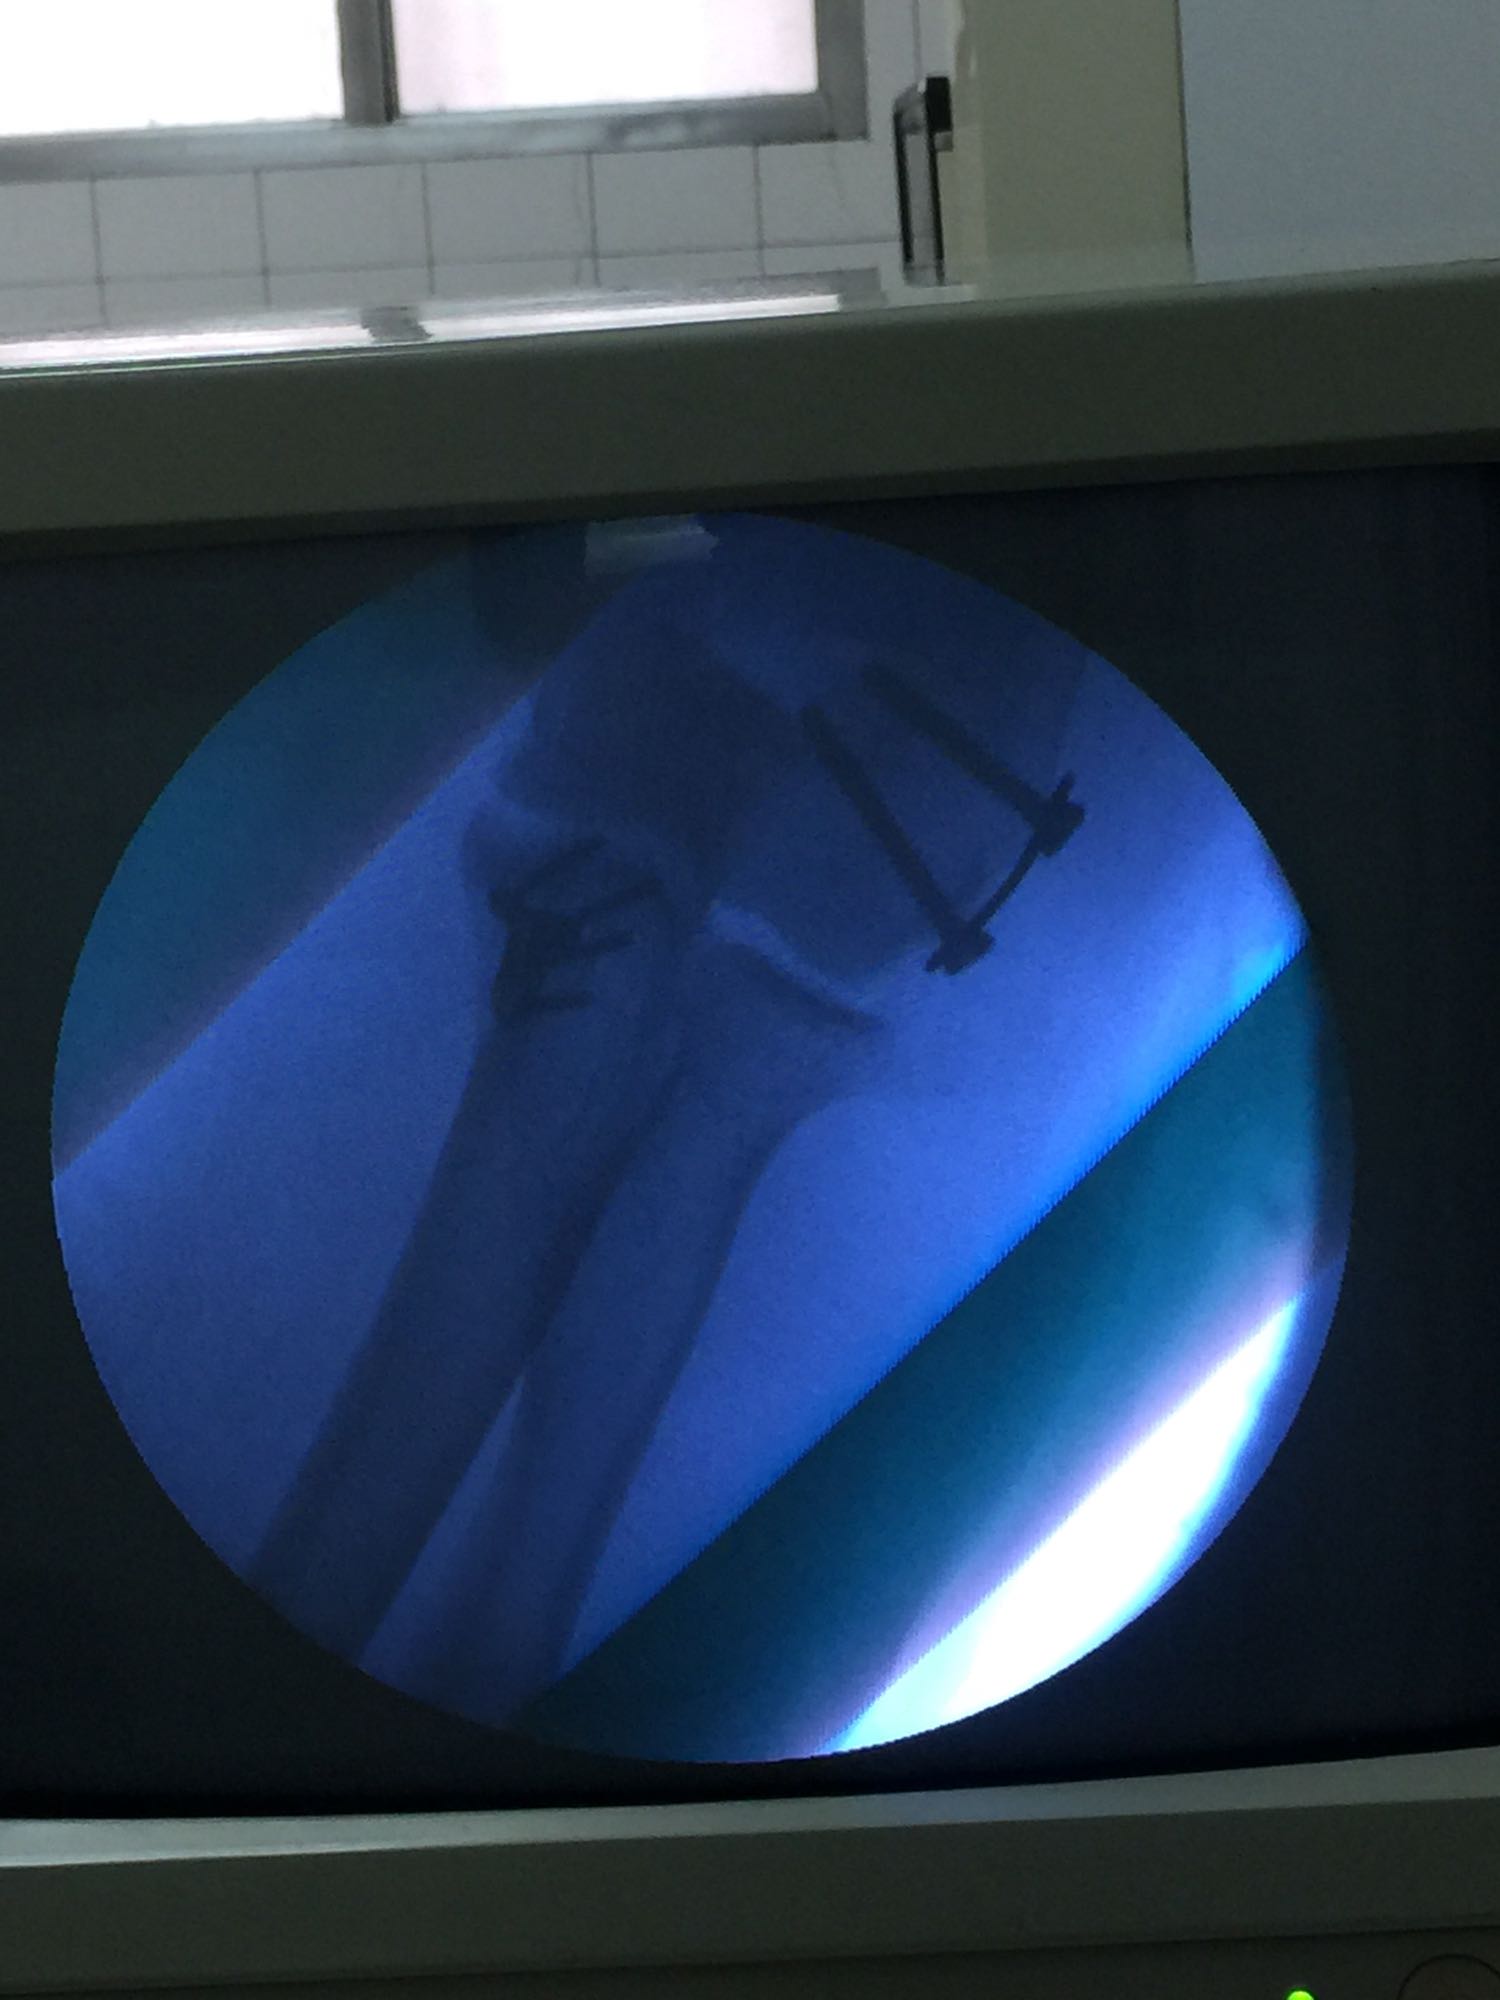

1、左尺骨冠状突骨折;2、左肱骨外髁撕脱骨折 治疗:入院后伤肢石膏外固定,给予局部冷敷消肿治疗,于伤后一周行骨折手术治疗,先行前内侧切口复位固定冠状突骨折,活动肘关节发现关节明显不稳定,随取外侧切口,复位固定肱骨外髁,修补外侧副韧带,肘关节明显稳定。术中术后片子如下